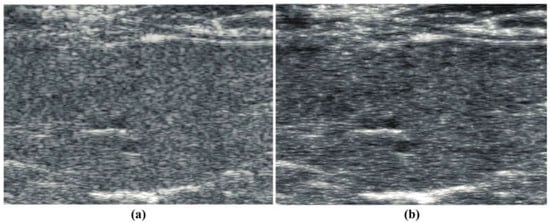

Similarly, a B-scan from a subject on a steatotic diet [] is shown in Figure 2a, demonstrating the classic general hyperechoic pattern as compared to normals. The corresponding “thru-scan” is shown in Figure 2b. Again, a pattern of possible fluid channels (hypoechoic spaces) along with small hyperechoic foci is seen throughout the background scattering amplitude. Compared with the normal liver’s constrained reconstruction (Figure 1b), the steatotic liver in Figure 2b appears more hyperechoic, and the hyperechoic spots are distributed throughout the liver. The speckle pattern within the liver in Figure 2a from the conventional envelope has a mean/standard deviation ratio of 1.97, close to the theoretical Rayleigh speckle ratio of 1.91 expected from ensembles of subresolved scatterers []. In comparison, the constrained power law reconstruction of Figure 2b has a mean/standard deviation ratio of 2.18, indicating a higher value of what Burkhardt termed as the “signal to noise” ratio of speckle patterns []. Similar trends are seen in the processing of human livers at 3 MHz, normal vs. steatotic, but these images are not available at this time for distribution, only by request.

Figure 2.

(a) Conventional B-scan at 15 MHz from a diet-induced steatotic mouse liver, in vivo. (b) constrained reconstruction from power law principles, which we call “thru-scan”, demonstrating a modified background and the emergence of specific hyperechoic points. The images are displayed conventionally using log-compressed 50 dB dynamic range grayscale.